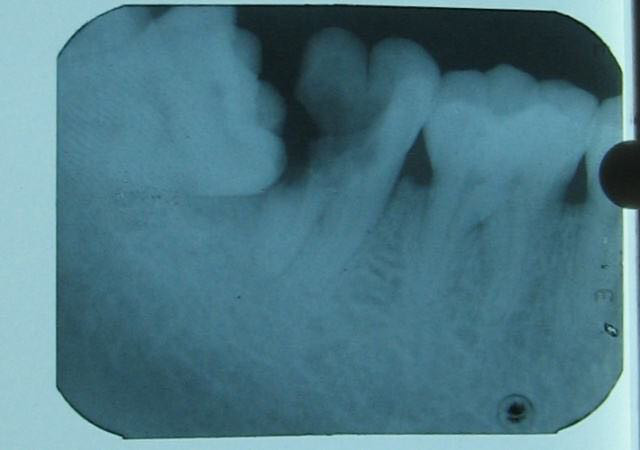

(图为智齿顶坏第二磨牙透视)

正解:正常情况下,牙齿肩并肩挤在一起相互支持。但多数情况下,智齿都是在扮演一个“麻烦制造者”的角色,有这样的邻居,对于第二恒磨牙来说可不是什么幸运的事:第二恒磨牙要么经常发炎,要么用力顶邻牙的后腰,反正终究难逃松动的命运。因此,尽早拔除智齿不但不会导致第二磨牙松动,反而会有利于第二磨牙安稳生长。